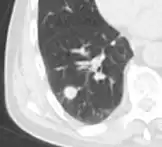

CT scan

For incidentally detected nodules on CT scan, Fleischner Society guidelines are given in table below. For multiple nodes, management is based on the most suspicious node.[8] These guidelines do not apply in lung cancer screening, in patients with immunosuppression, or in patients with known primary cancer.[8]